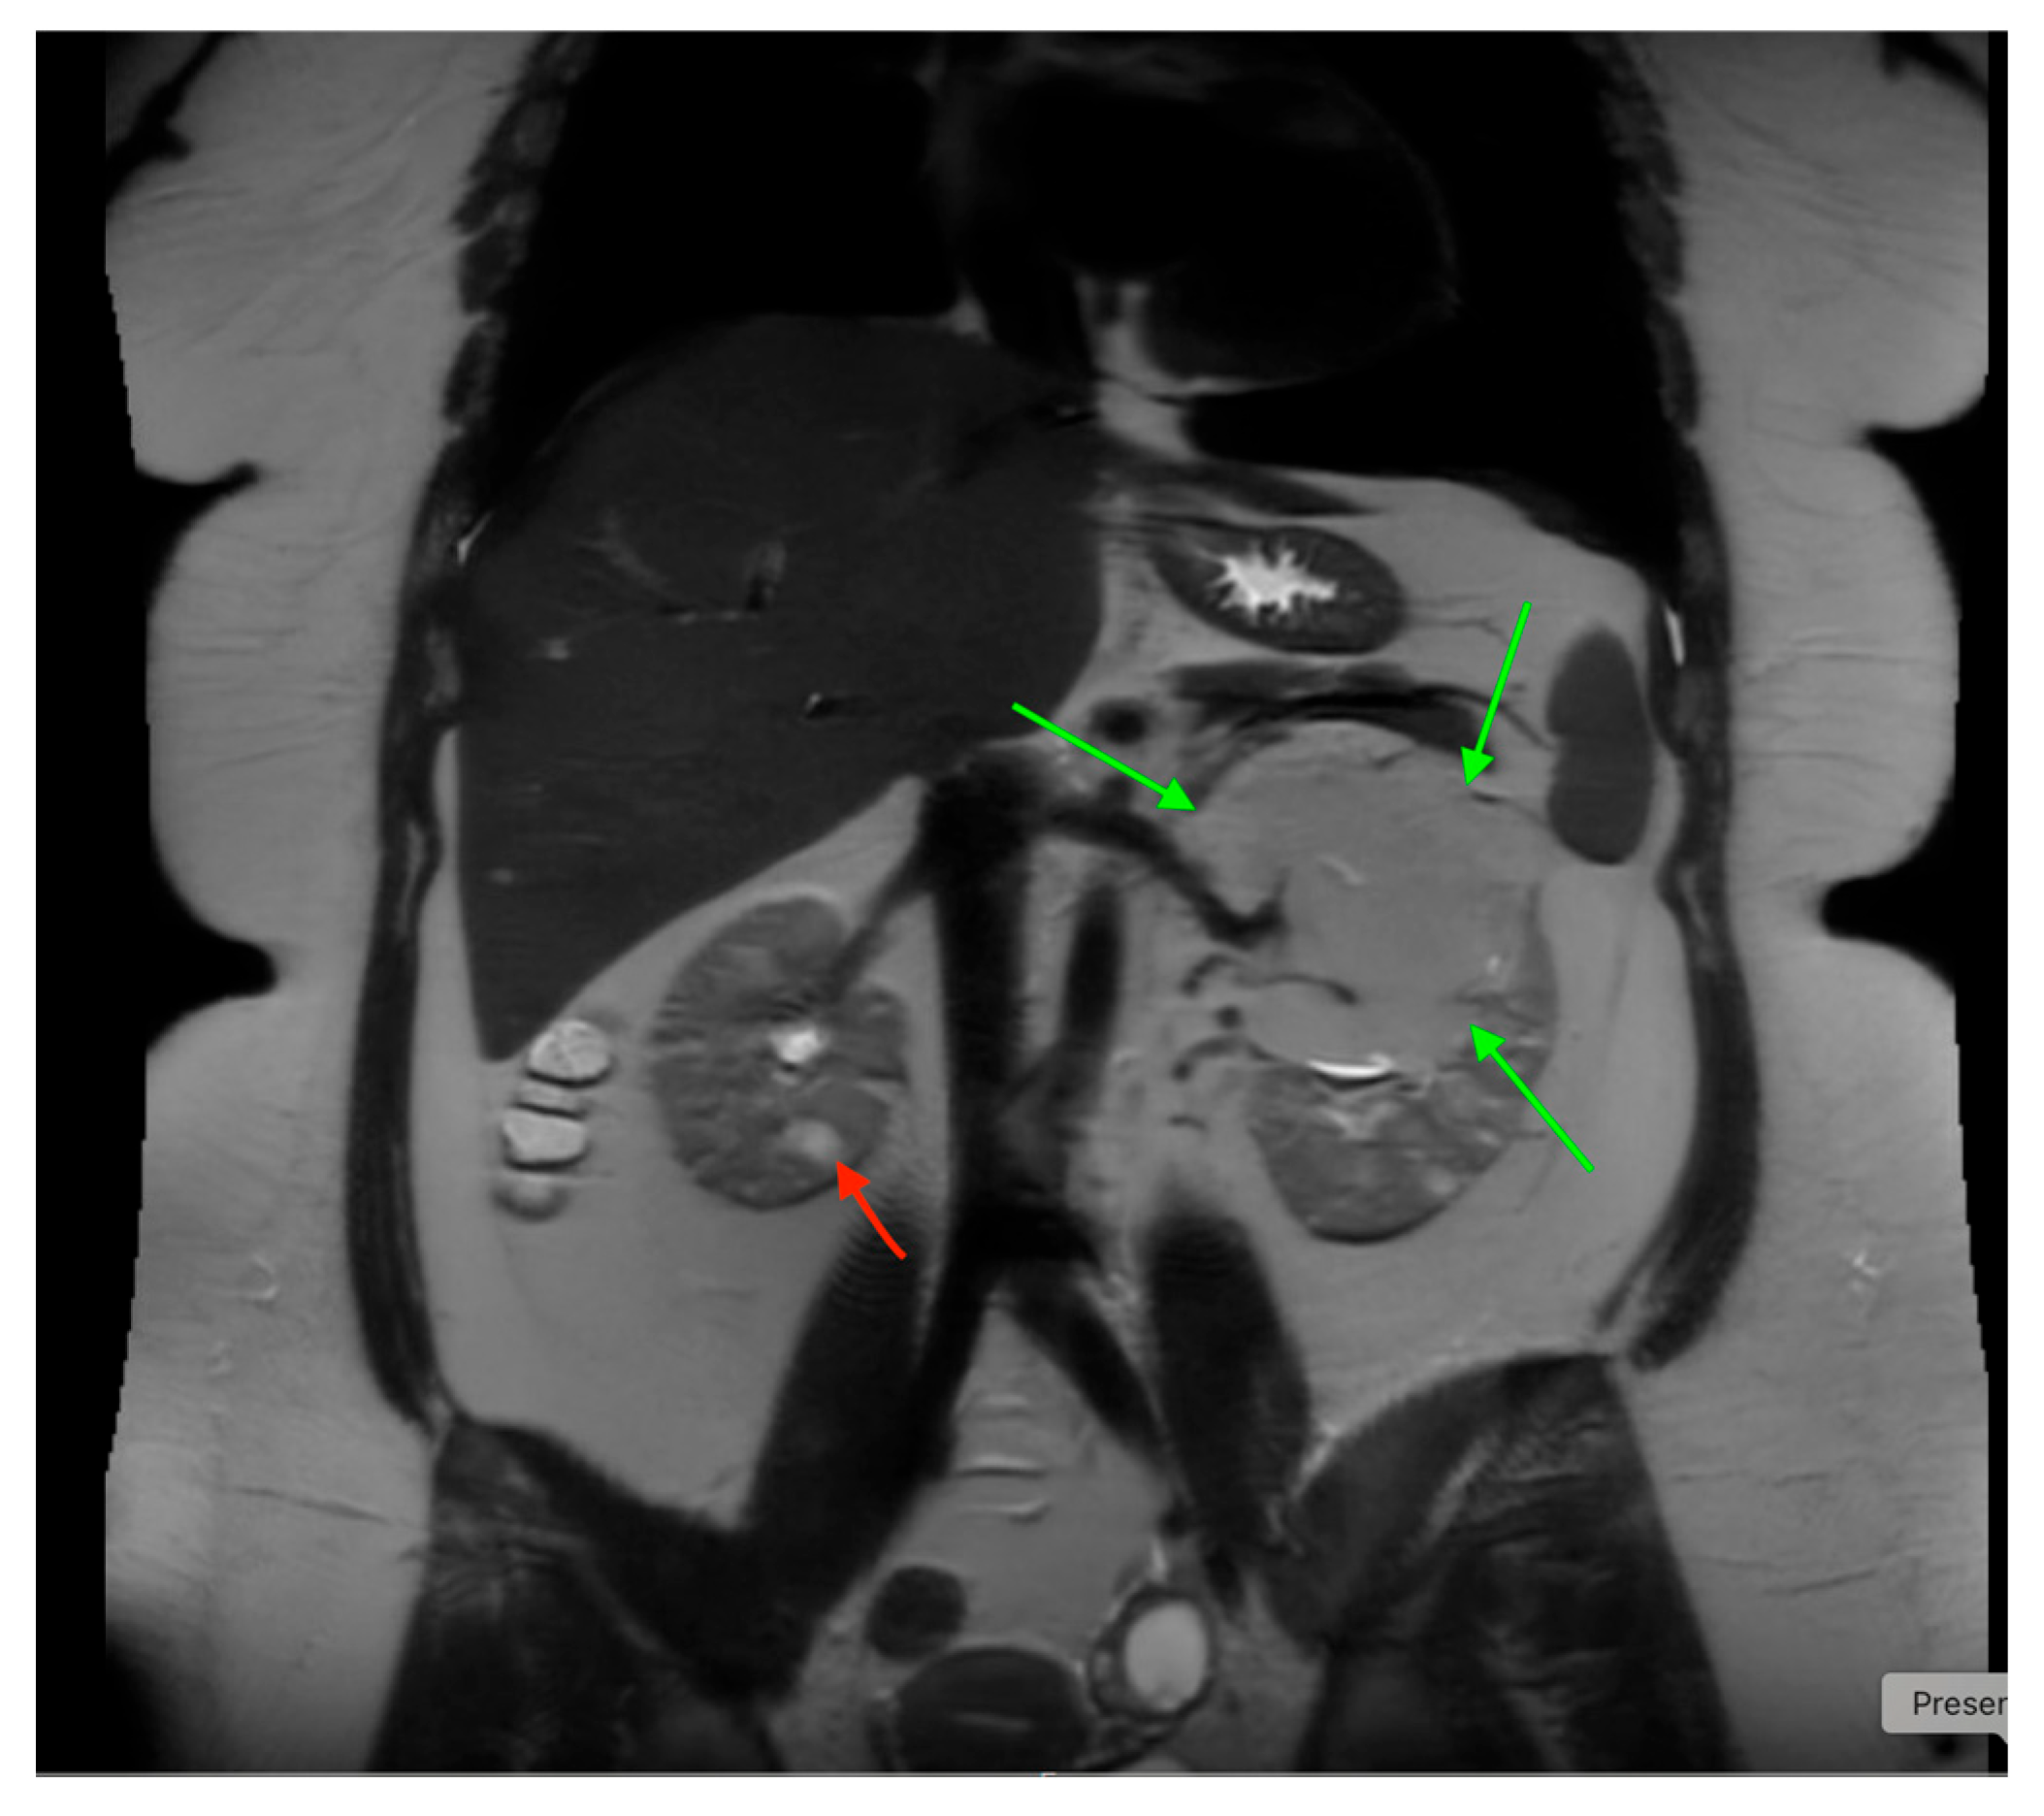

- A horseshoe kidney is the most common renal fusion anomaly, occurring in about 1 in 400 live births. In this condition, both kidneys are fused at their lower poles, forming a “horseshoe” shape (Figure 14)

- Renal ectopia occurs in approximately 1 in 900 births and is typically unilateral. In about 40% of cases, the ectopic kidney is located in the pelvis. Crossed ectopia occurs when one kidney crosses the midline and fuses with the other, often resulting in a “crossed-fused” appearance.